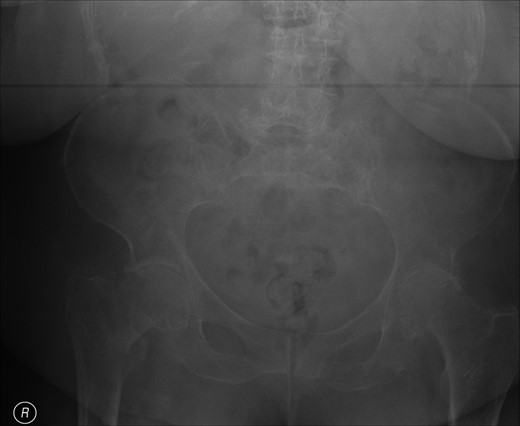

A lady of 88 years old presented with pain in her right hip following a fall at home. Radiographs of the proximal femur revealed an extra-capsular fracture, as shown in Fig. 1. She was taken to the operating theatre within 48 h. In an uncomplicated procedure, the fracture was fixed with a 75-mm, 135°, dynamic hip screw (DHS). A short (25-mm) barrel with four-hole plate was used. Intraoperative screening images are shown in Fig. 2. This position was accepted.